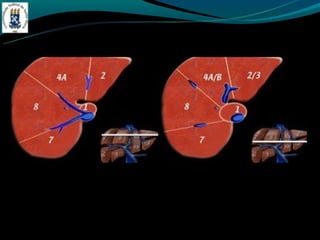

SEGMENTAÇAO DE COUINAUD

-